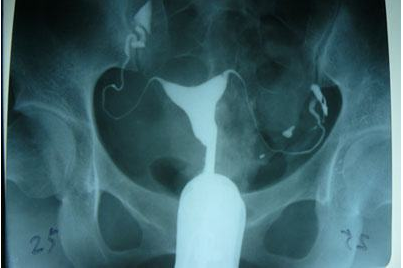

輸卵管造影是用來檢查女性輸卵管通暢與否的一種檢測(cè)方法。目前,輸卵管造影是臨床上應(yīng)用較為廣泛的方法之一。造影是通過導(dǎo)管經(jīng)陰道、宮頸、子宮腔直接插向子宮角的輸卵管開口處,對(duì)著輸卵管推注造影劑而使輸卵管顯影,進(jìn)而了解輸卵管是否通暢、阻塞部位及宮腔形態(tài)的一種檢查方法。

輸卵管造影檢查可直觀了解輸卵管是否通暢以及阻塞的部位,觀察子宮腔的大小、形態(tài)、有無畸形及有無宮腔粘連或占位性病變,而且不孕不育專科醫(yī)院所采用的造影劑都是對(duì)人體沒有傷害可吸收的,對(duì)輕微的輸卵管堵塞患者還能疏通治療,可以在次月實(shí)施備孕。

推注造影劑力,造影劑進(jìn)入盆腔緩慢,在停注造影劑數(shù)十分鐘后,可見造影劑在盆腔內(nèi)彌散,但彌散欠佳。

輸卵管完全不顯影或顯影一段后不再顯影,且造影劑注入到一定劑量時(shí)阻力加大,盆腔內(nèi)無造影劑影彌散。

造影劑積聚在輸卵管內(nèi),輸卵管常擴(kuò)張呈囊狀或臘腸狀,以遠(yuǎn)端明顯,多伴有輸卵管傘端阻塞。盆腔內(nèi)一般無造影劑影彌散。